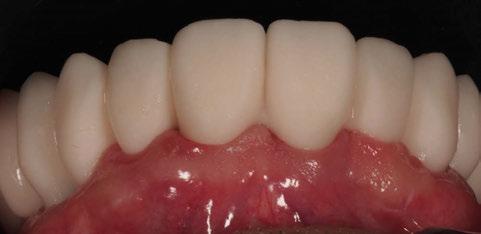

4. Fase protésica provisional

Una vez colocados los pilares provisionales de titanio, se adaptó la férula pick-up modificada y se verificó su correcto asentamiento de los pilares a través de los orificios de ésta. A continuación, se recapturó la férula a los pilares de titanio mediante resina acrílica autopolimerizable (Enamel Temp

Plus®) y, una vez polimerizada, se tomó un registro de mordida, se desatornillaron los pilares y se retiraron de boca. Seguidamente, se atornillaron los análogos verificando que no hubiera movilidad de ningún pilar y se envió al laboratorio para el acabado y pulido final, eliminando todo el soporte y añadiendo un refuerzo metálico por palatino. En boca, se colocaron los tapones de cicatrización de los transepiteliales y se le explicaron las recomendaciones postquirúrgicas y medicación necesaria. Instruimos al laboratorio a dejar los perfiles de emergencia lo más estrechos posibles y los pónticos ovoides entrando unos 3 mm en cada alveolo a fin de preservar la arquitectura gingival presente.

A las 24 horas se citó al paciente nuevamente, se atornilló el provisional en boca y se realizó una

Figura 24. Provisional finalizado tras acabado y pulido en el laboratorio.

Figura 25. Provisional finalizado tras acabado y pulido en el laboratorio.

Figura 26. Entrega del provisional de carga inmediata a las 24 horas.

Figura 27. Ortopantomografía del provisional atornillado en boca para verificar ajuste.

ortopantomografía de verificación del ajuste pasivo de todos los implantes. Por último, tapamos las chimeneas con teflón y resina provisional y se chequeó nuevamente la oclusión, dando nuevamente las instrucciones de higiene y mantenimiento de la prótesis provisional (Figuras 24-27).